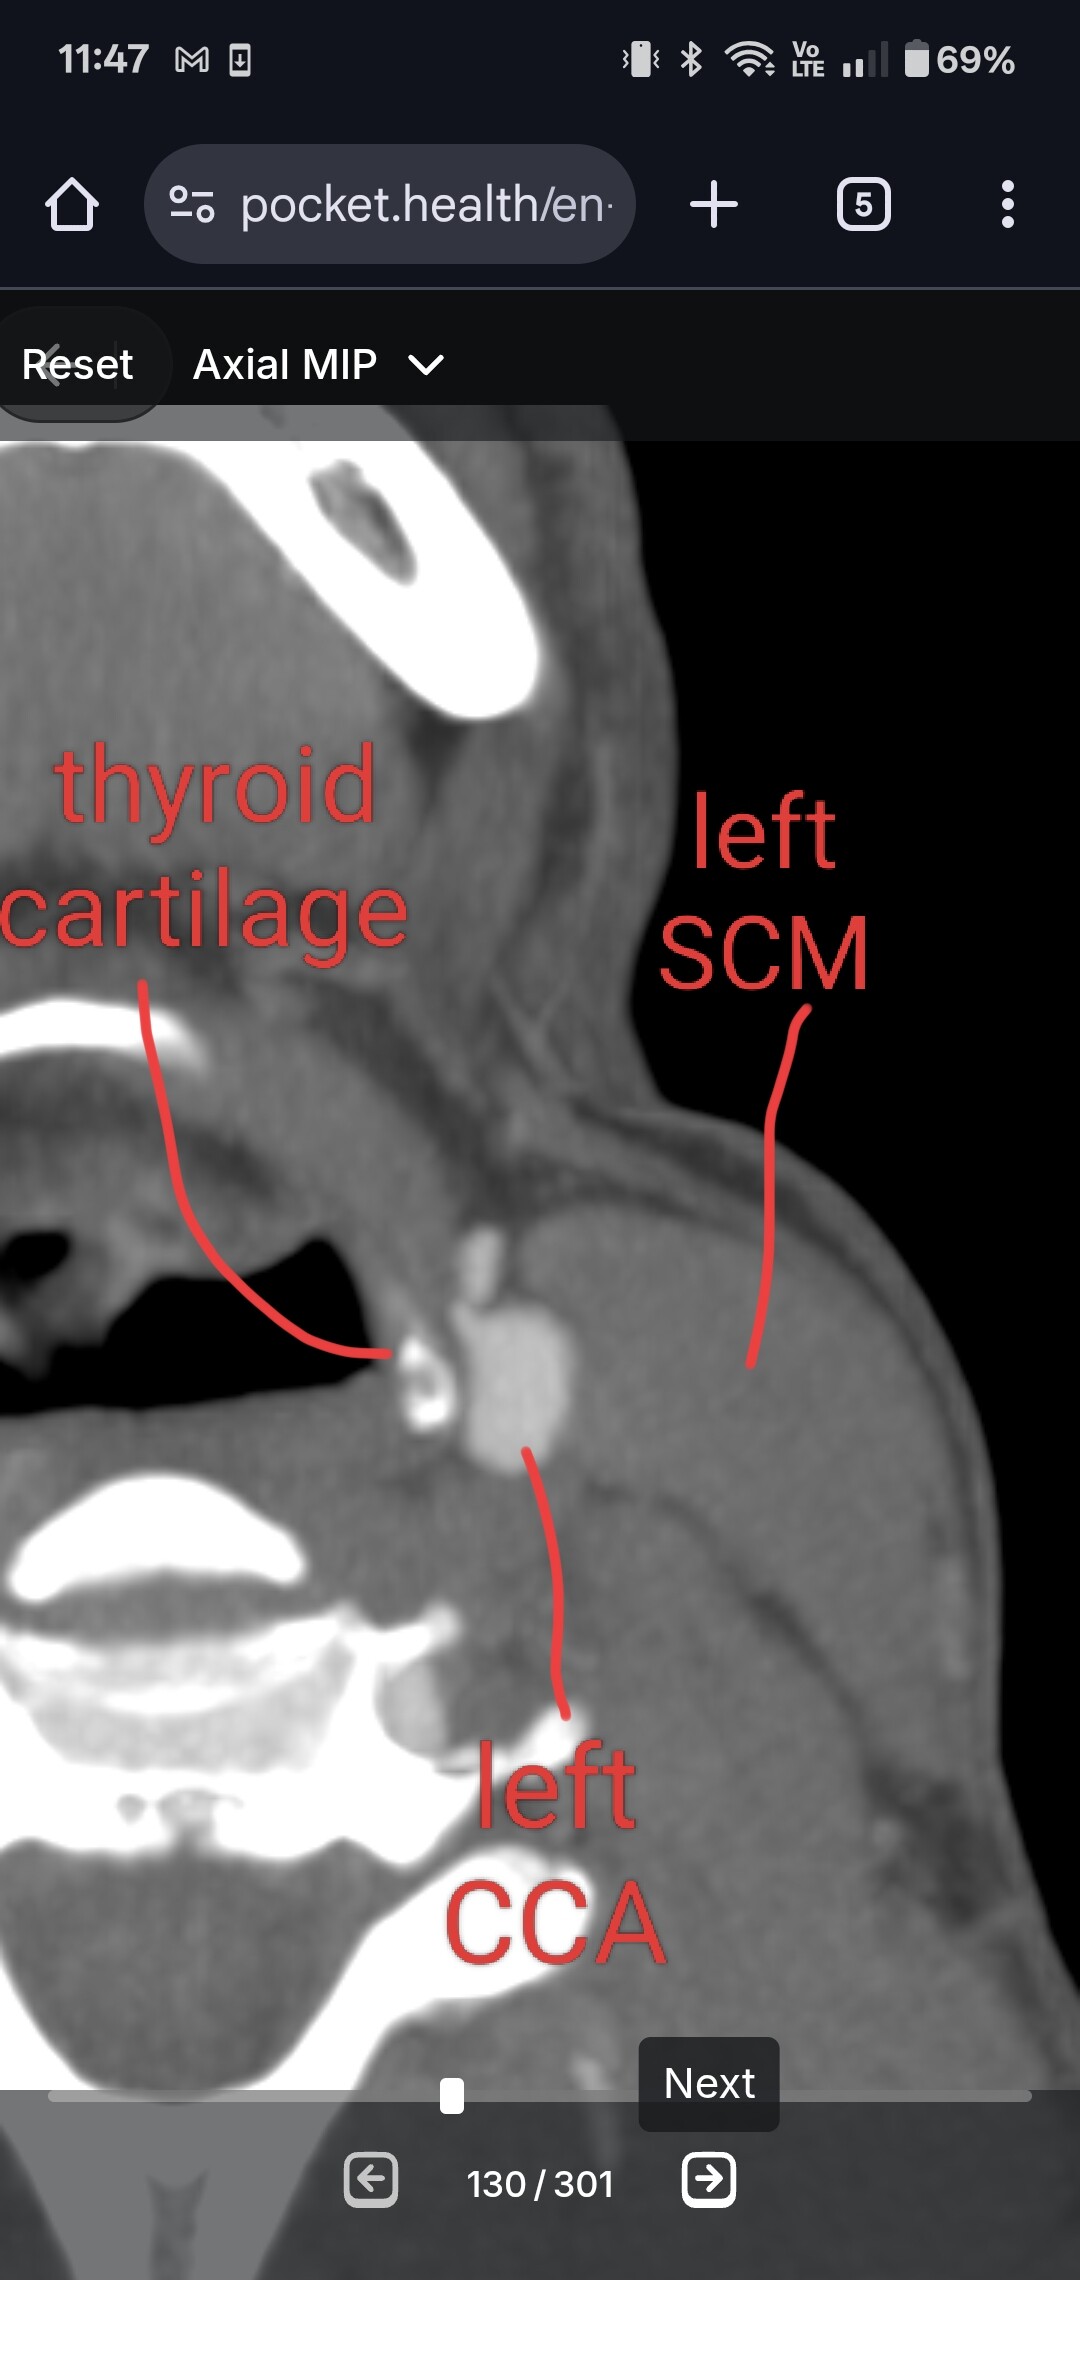

I discovered the carotid involvement on my own by going through my CT imaging. Then I got a neuroradiology second opinion that confirmed some of it, then I took it to my ENT who confirmed all of it. Both styloids are compressing my IJVs against C1, but they are also compressed between SCMs and anterior scalenes. My dangerous conditions is my left greater horn of my hyoid is digging into my ICA (directly above the carotid sinus) and my thyroid cartilage is compressing my CCA. Surgery next week for left styloidectomy and trim of left greater horn. Surgeon is going to assess the thyroid cartilage more while I’m opened up. I live in Nova Scotia, Canada and am getting surgery here.

Way to do your research! What image is that where you labeled scalines and Scm muscles? Are you able to see those muscles in a CTA or CTV? You have clearly done your research.

@Luckee7 yes, you can see the SCMs and scalenes on any CT with contrast. I’ll be able to take a look if you can figure out the files!